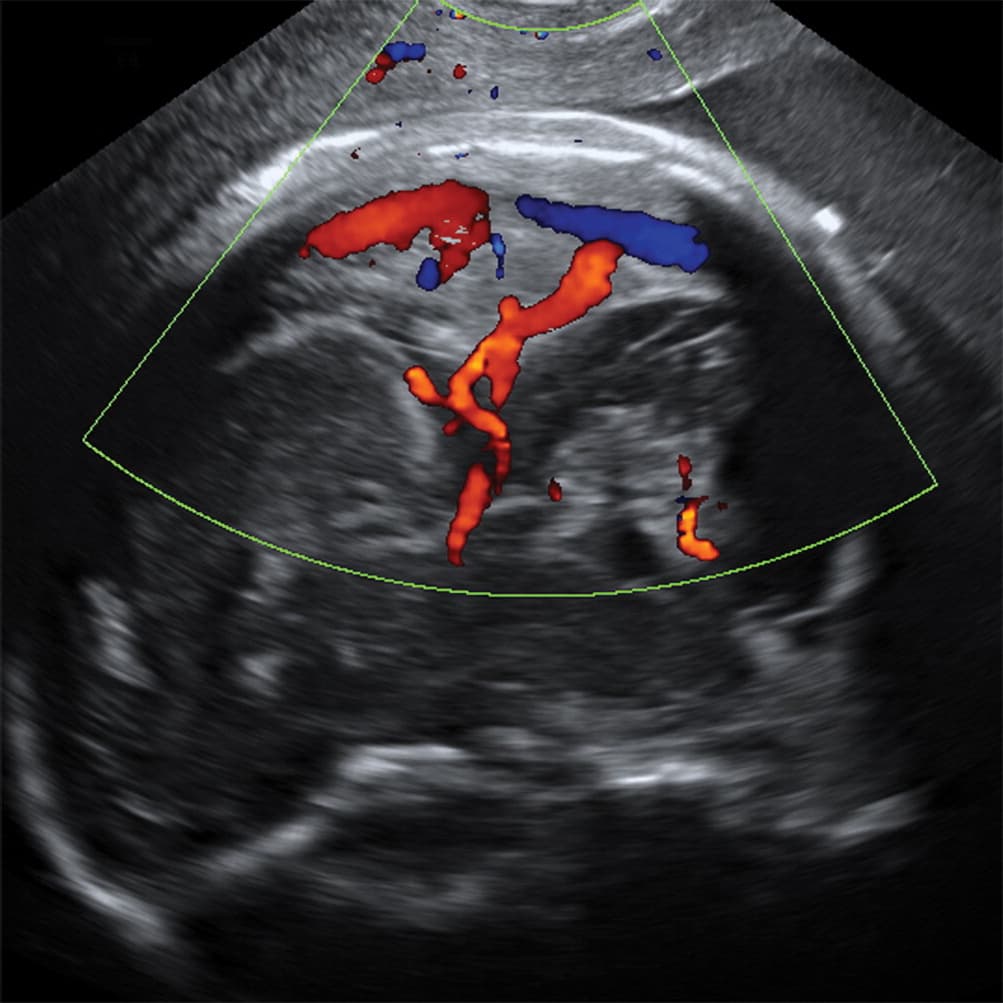

Investigadores brasileños difundieron este martes el mayor número hasta ahora disponible de imágenes computarizadas, resonancias magnéticas y ultrasonidos, de bebés y fetos infectados con el virus del Zika. El daño es mucho mayor del que anticipaban.

Así describe la radióloga brasileña Fernanda Tovar-Moll lo que vio al analizar centenares de imágenes computarizadas, resonancias magnéticas y ultrasonidos de 45 bebés que se contagiaron de zika en el vientre materno en el estado de Paraíba, en el noreste del país, donde el brote ha sido severo.

Todavía se desconoce exactamente cómo el zika logra penetrar la placenta y contagiar al feto, cuando la mayoría de los víruses no lo consigue. Tampoco el por qué solo algunas mujeres embarazadas que están infectadas de zika transmiten el virus a su feto. Pero se cree que el daño mayor ocurre durante el primer trimestre. “A las 20-24 semanas ya se pueden ver la mayoría de las anomalías en un ultrasonido”, comentó Tovar-Moll.